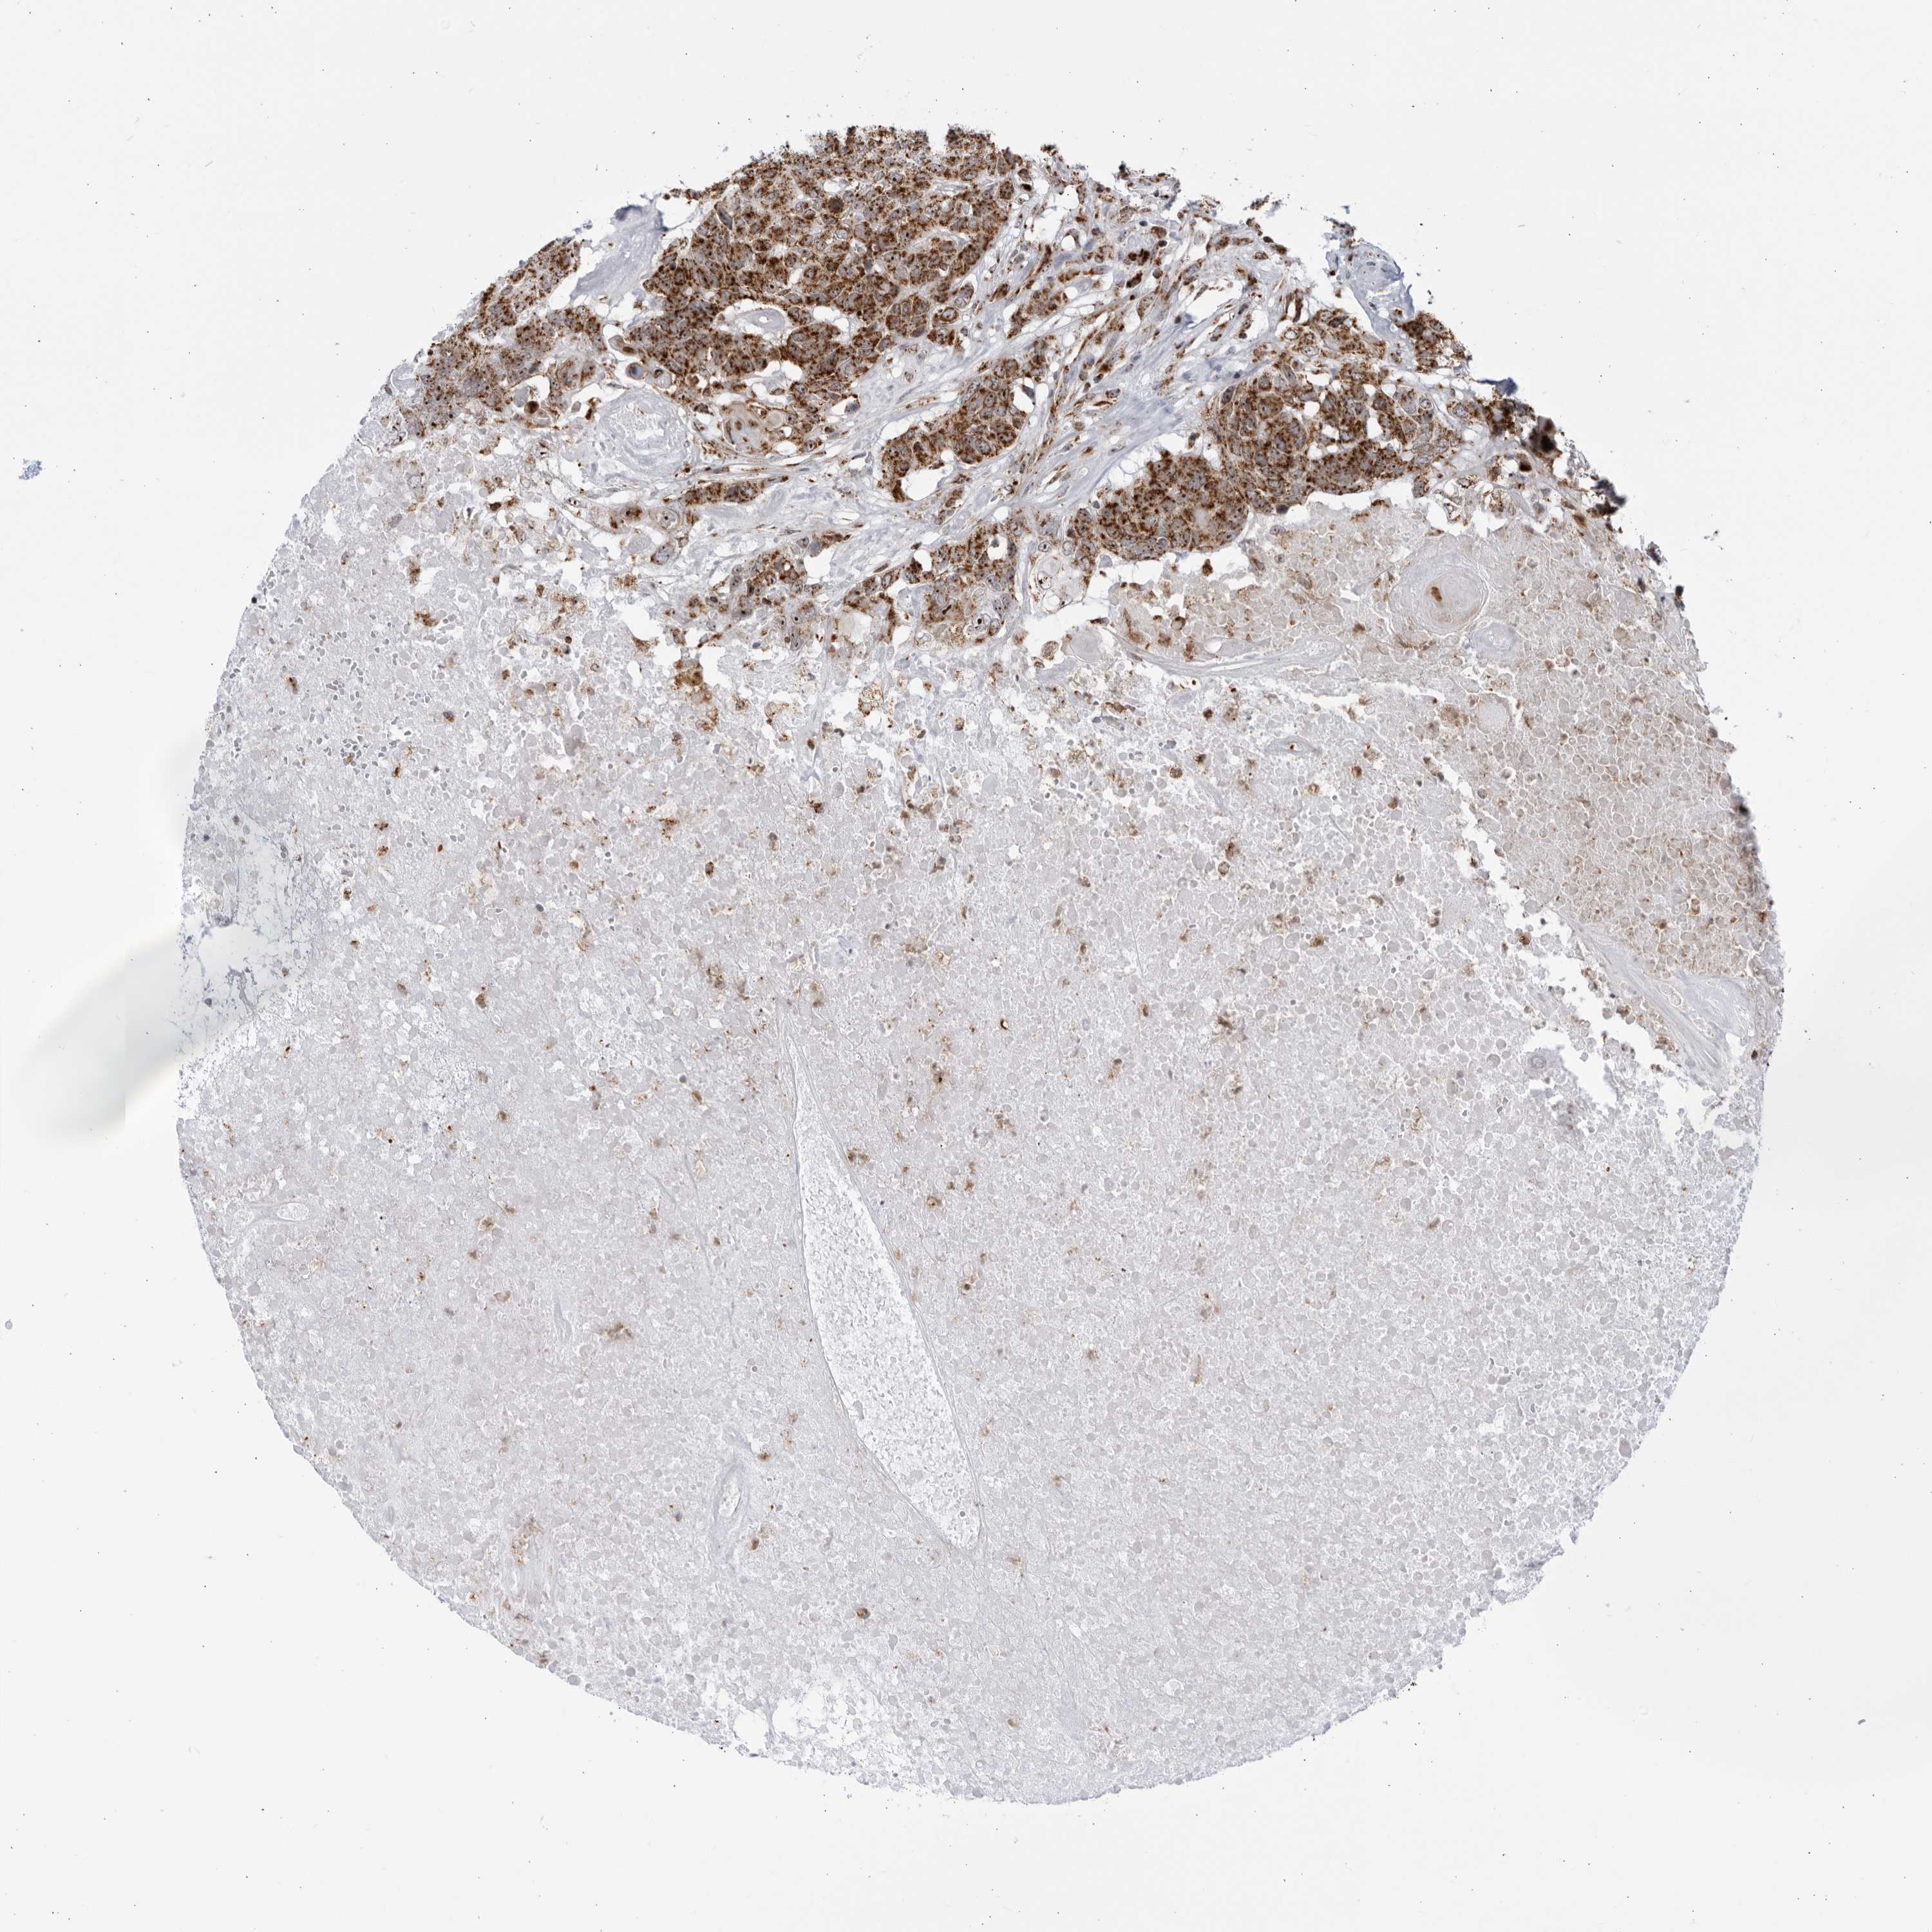

HEAD AND NECK CANCER - Protein expressioni

A mouse-over function shows sample information and annotation data. Click on an image to view it in a full screen mode. Samples can be filtered based on level of antibody staining by selecting one or several of the following categories: high, medium, low and not detected. The assay and annotation is described here.

Antibody stainingi

Antibody staining in the annotated cell types in the current human tissue is reported as not detected, low, medium, or high, based on conventional immunohistochemistry profiling in selected tissues. This score is based on the combination of the staining intensity and fraction of stained cells.

Each image is clickable and will lead to virtual microscopy that enables deeper exploration of all samples and also displays staining intensity scores, fraction scores and subcellular localization as well as patient and tissue information for each sample.

Antibody HPA028606

Staining

High

Medium

Low

Not detected

Intensity

Strong

Moderate

Weak

Negative

Quantity

>75%

75%-25%

<25%

None

Location

Nuclear

Cytoplasmic/membranous

Cytoplasmic/membranous,nuclear

Squamous cell carcinoma, NOS

Squamous cell carcinoma, metastatic, NOS

Adenocarcinoma, NOS

Adenoma, NOS